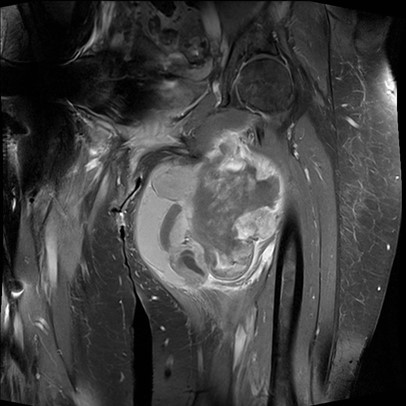

MRI